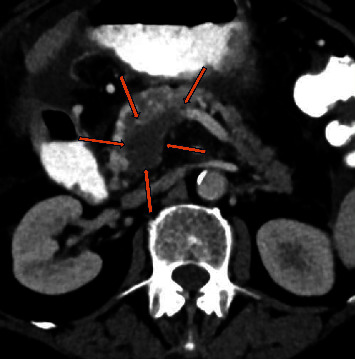

缺血性肠病被认为是厌氧菌感染的高危因素,因为缺血性肠道是厌氧菌生长的理想场所。在此,我们介绍了一例结肠癌晚期患者的病例,该患者罕见地出现了消化道出血和菌血症,病因是一种罕见的厌氧革兰阳性菌--副梭状芽孢杆菌。该患者在慢性肠系膜上静脉-门静脉肿瘤血栓形成和异位静脉曲张破裂的情况下曾多次出现血崩,而菌血症是动脉缺血和静脉充血共同导致的肠道缺血的意外并发症。

Ischemic bowel disease is considered a high-risk factor for infection from anaerobic bacteria, as the ischemic bowel is the perfect ground for their development. Herein, we present the case of an advance stage colon cancer patient with a rare cause of gastrointestinal bleeding and bacteremia due to Clostridium paraputrificum, a rare anaerobic Gram-positive bacterium. The patient had presented with several episodes of hematochezia in the context of chronic superior mesenteric-portal vein tumor thrombosis and rupture of ectopic varices, and the bacteremia was an unexpected complication of the bowel ischemia due to a combination of arterial ischemia and venous congestion.